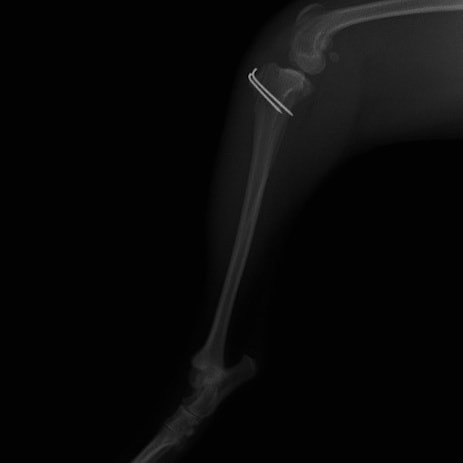

■ 症例24 キャバリア 7か月

左右膝蓋骨内方脱臼(左:グレードⅣ 右:グレードⅢ)

以前から左右後肢の跛行が認められ、整形外科学的検査・レントゲン検査により左右の膝蓋骨脱臼が認められた。症状が重度である左膝の膝蓋骨脱臼整復術を行った。外科手技は縫工筋及び内側広筋の解放、脛骨粗面の外側転位、滑車ブロック形造溝術、内外側関節方の縫縮を実施した。術後一か月時点で、左の膝蓋骨は安定しており経過は良好である。

本症例は成長期における重度の膝蓋骨脱臼であり、術後の再発の可能性もあるため、経過をしっかりと観察していく必要がある。また、今回手術を実施していない右膝に関しても経過を観察し、手術を検討していくこととする。